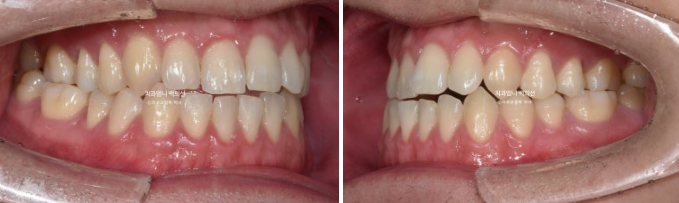

This is what it looked like after wearing all the aligners for one year.

The space between the front teeth closed well, and the open bite was also resolved.

24.07

The upper teeth now overlap the lower teeth properly in the front.

For improvement of the bite, midline, and premolar rotation, we went into a remaking phase, and from August to November 2024, the patient wore an additional set of aligners for 4 months.

The molar bite improved stably, but a very slight midline discrepancy remained, so we made one more additional set.

In total, the aligners were remade twice.

After wearing the aligners for another 3 months from December 2024 to February 2025, the treatment was completed.

You can see a well-aligned midline and a good bite.

Now let’s compare before and after.